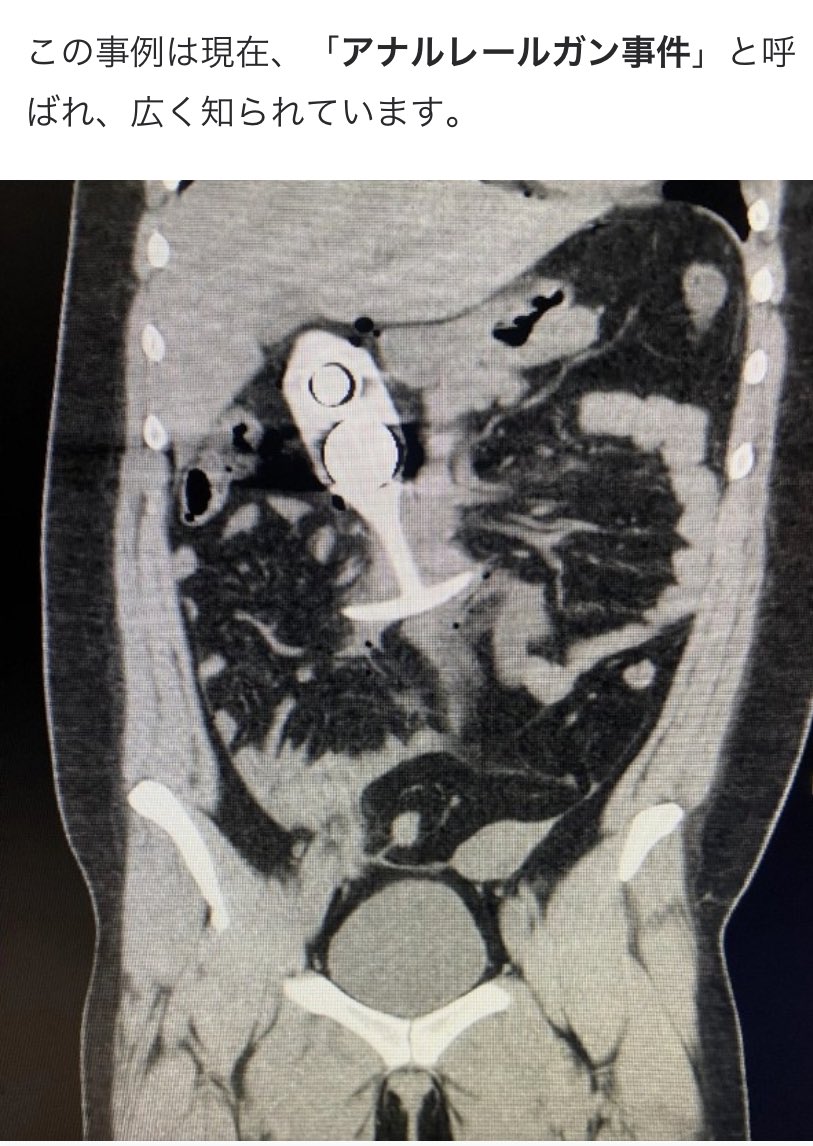

直腸内に長さ20センチ砲弾「自分で入れた」男性、仏病院が治療

1770175943084.jpg-(70095 B)

70095 B

キタ━━━(゚∀゚)━━━!!